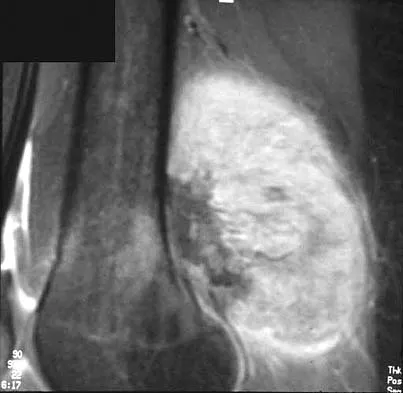

A 28-year-old professional dancer reports a 3-month history of progressive pain in the posterior aspect of the left ankle. Her symptoms are worse when she assumes the en pointe position. Examination reveals tenderness to palpation at the posterolateral aspect of the ankle posterior to the peroneal tendons which is made worse with passive plantar flexion. There is no nodularity, fluctuance, or tenderness of the Achilles tendon. The neurovascular examination is unremarkable. A lateral radiograph and MRI scan are shown in Figures 16a and 16b, respectively. Management should consist of

The imaging studies reveal findings typical of the os trigonum syndrome. This condition results from inflammation between the os trigonum and the adjacent talus. The symptoms of posterior ankle pain are exacerbated by plantar flexion, which stresses the fibrous union between these two bones. Definitive management of the high-level athlete involves excision of the os trigonum from a medial approach, although arthroscopic excision has also been described. The os trigonum is not an intra-articular structure; therefore, ankle arthroscopy is neither diagnostic nor therapeutic. Abramowitz Y, Wollstein R, Barzilay Y, et al: Outcome of resection of a symptomatic os trigonum. J Bone Joint Surg Am 2003;85:1051-1057. Mouhsine E, Crevoisier X, Leyvraz P, et al: Post-traumatic overload or acute syndrome of the os trigonum: A possible cause of posterior ankle impingement. Knee Surg Sports Traumatol Arthrosc 2004;12:250-253.